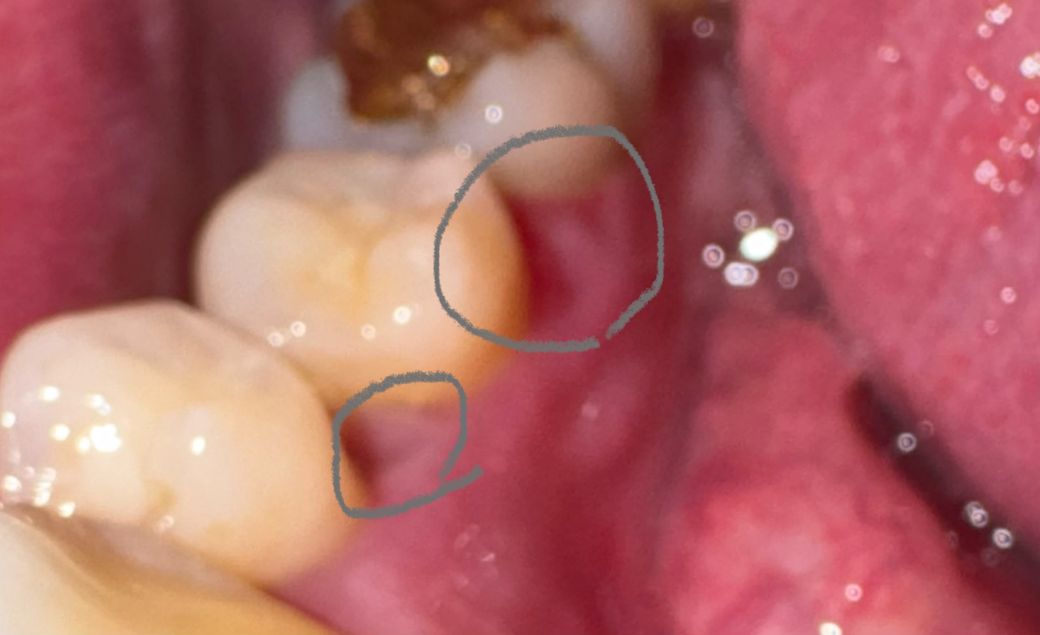

치간유두부위? 치아안쪽 치아사이 까짐 봐주세요

치아 안쪽 치아사이 치간유두부위?쪽이 살이 까져서

다른 잇몸에 비해서 붉어보이는데 치실이랑 치간칫솔

사용중에 피가 나가서 사진속 동그라미 부분이 살이

까져서 붉게 보이는데 치과에 가봐야될까요?

아니면 따로 연고나 주의할점이 있을까요?

• 1번 째 사진